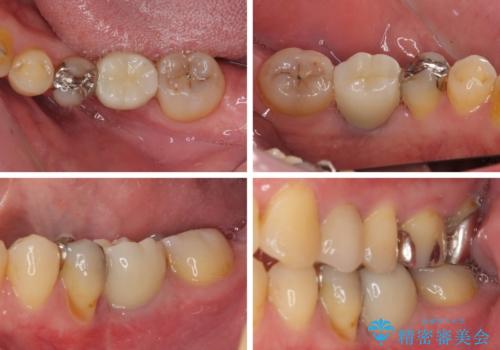

矯正治療でインプラント埋入を行い、矯正治療後に気になる前歯と合わせてオールセラミッククラウンによる補綴治療を行うこととしました。

骨造成や歯肉移植など、治癒期間の長い処置を必要としたため治療期間は長くなりましたが、安定した咬み合わせと整った歯列となり、患者様には大変満足していただきました。